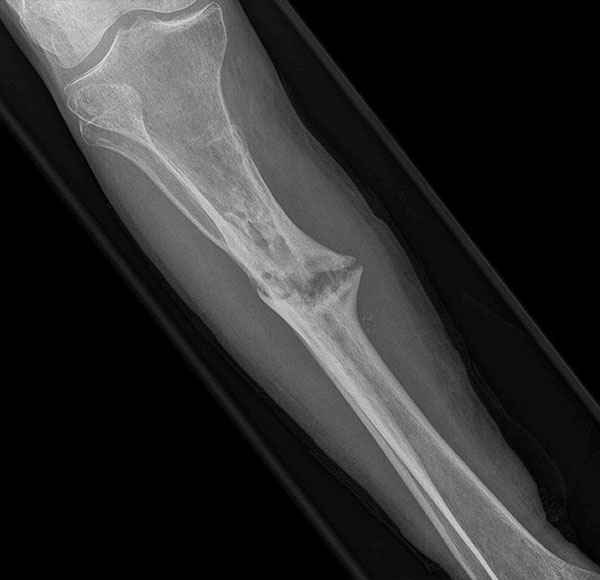

- Focus Area Reconstructive Surgery & Non-Surgical Management to Improve Bone Healing

- Sponsor DoD PRORP

- Primary Objective Observational outcome study of peripheral nerve repair and reconstruction